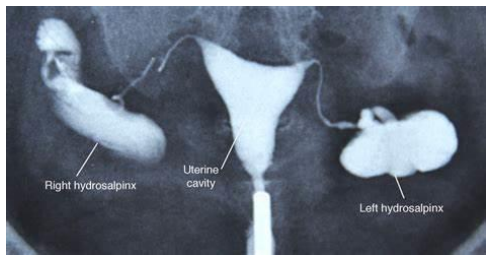

هیستروسالپنگوگرافی (Hysterosalpingography – HSG) یک روش تصویربرداری تخصصی است که با استفاده از اشعه ایکس و تزریق ماده حاجب به داخل رحم، وضعیت حفره‌ی رحمی و باز بودن لوله‌های فالوپ را بررسی می‌کند. این روش یکی از مهم‌ترین آزمون‌های تشخیصی در ارزیابی اولیه ناباروری زنان محسوب می‌شود، زیرا بسیاری از موارد ناباروری به دلیل انسداد لوله‌های فالوپ رخ می‌دهد.

در این روش، پس از تزریق ماده حاجب، تصاویر متعددی از رحم و لوله‌ها گرفته می‌شود و پزشک می‌تواند شکل غیرطبیعی رحم، پولیپ، فیبروم، چسبندگی، سپتوم و مشکلات ساختاری دیگر را شناسایی کند.

یکی از مهم‌ترین علل ناباروری زنان، بسته‌بودن کامل یا نسبی لوله‌های فالوپ است. هیستروسالپنگوگرافی بهترین روش برای نمایش مسیر لوله‌ها و تشخیص محل دقیق انسداد به شمار می‌رود.

مشکلات ساختاری رحم مانند رحم سپتوم‌دار، دیواره رحمی، رحم دوشاخ یا تغییر شکل ناشی از چسبندگی‌ها قابل مشاهده هستند.

پولیپ، فیبروم داخل‌حفره‌ای، چسبندگی آشرمن، بقایای بارداری و ناهنجاری‌های مخاط رحم با HSG قابل شناسایی هستند.